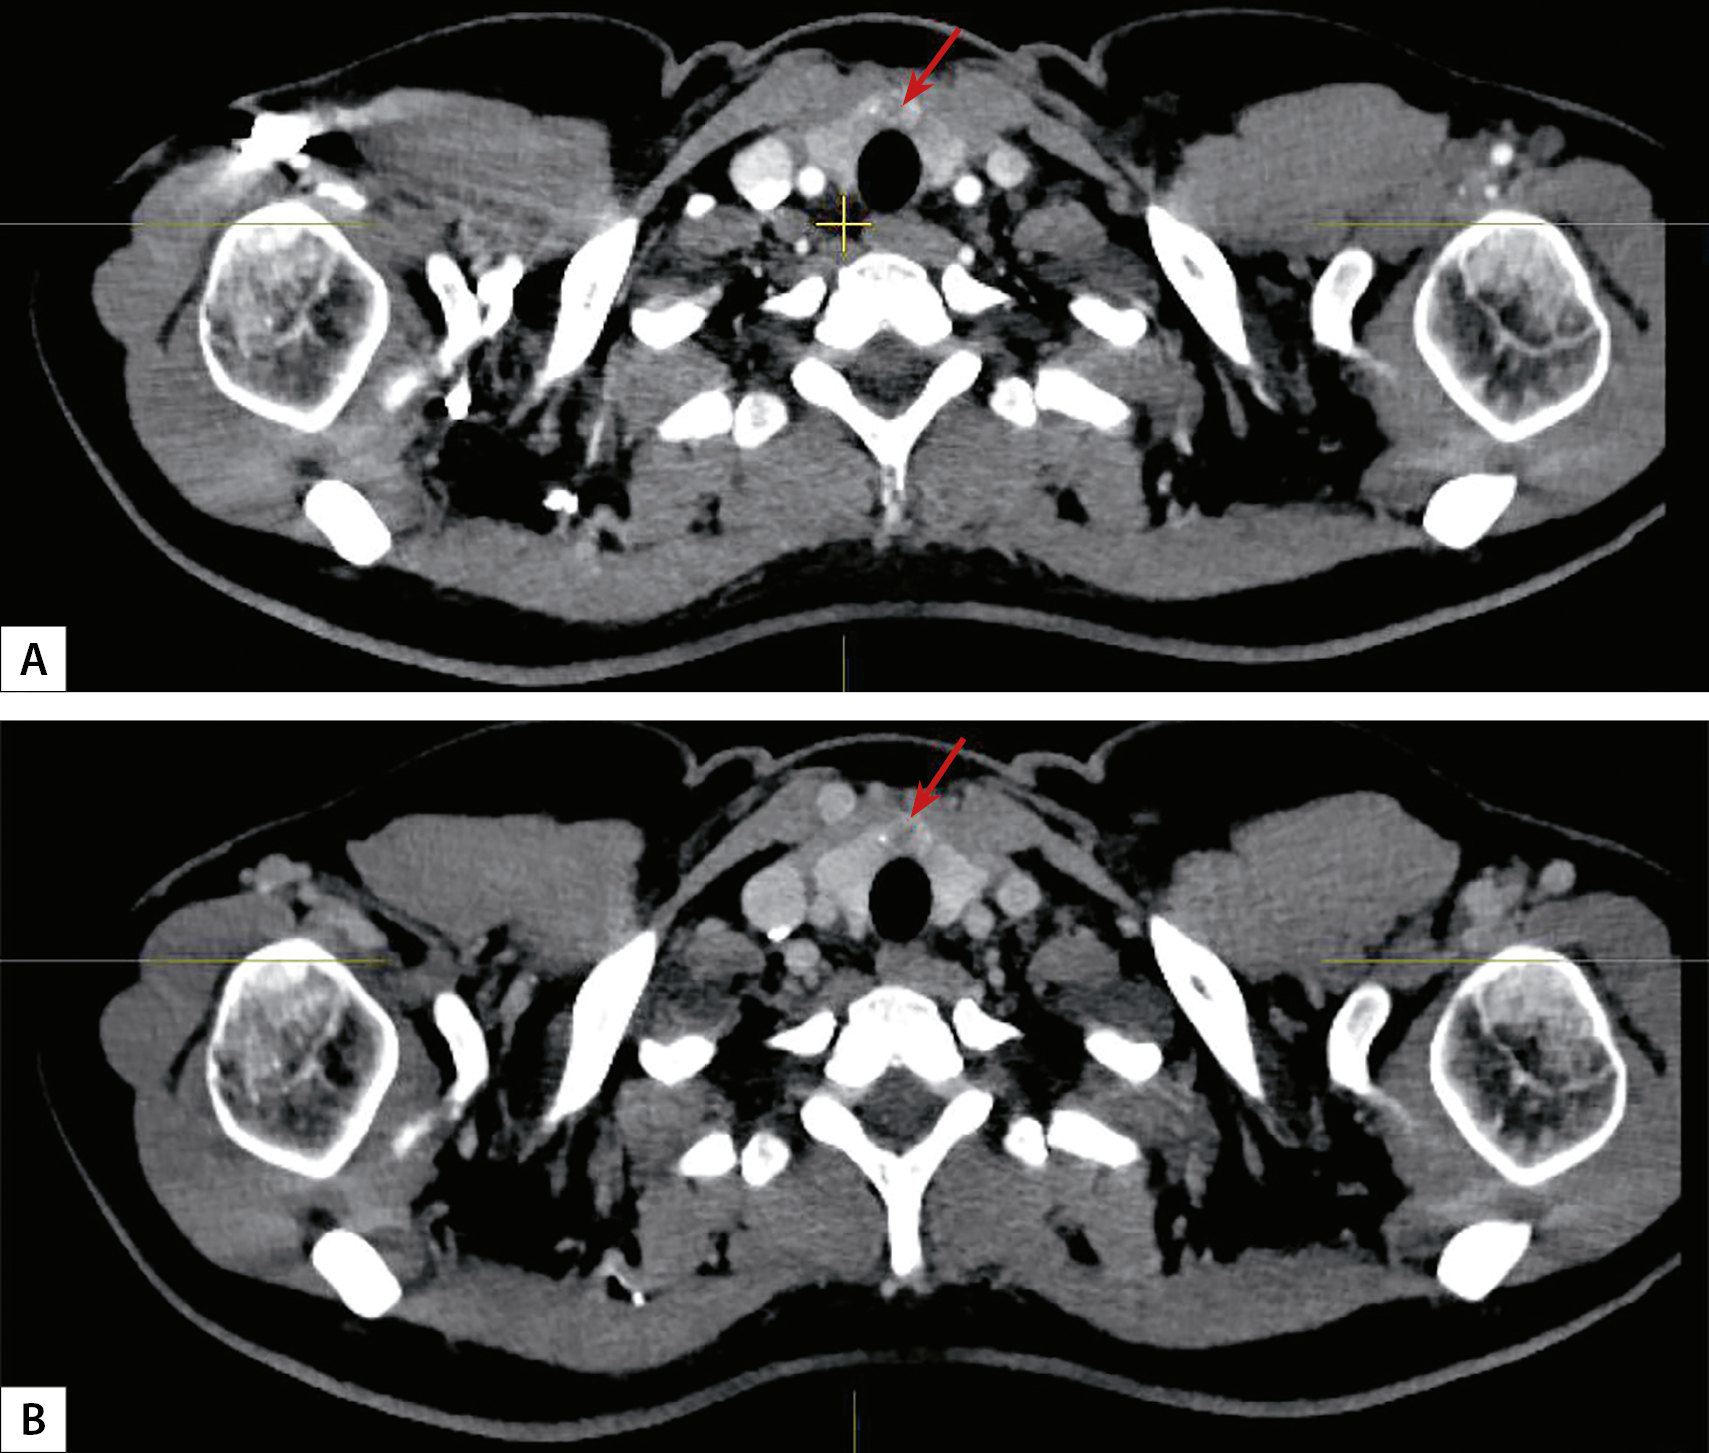

6. Рисунок 6. КТ-картина кальцинатов щитовидной железы (кальцинаты указаны стрелкой). А — микрокальцинат, В — макрокальцинат, С — периферическая кальцификация образований. | |